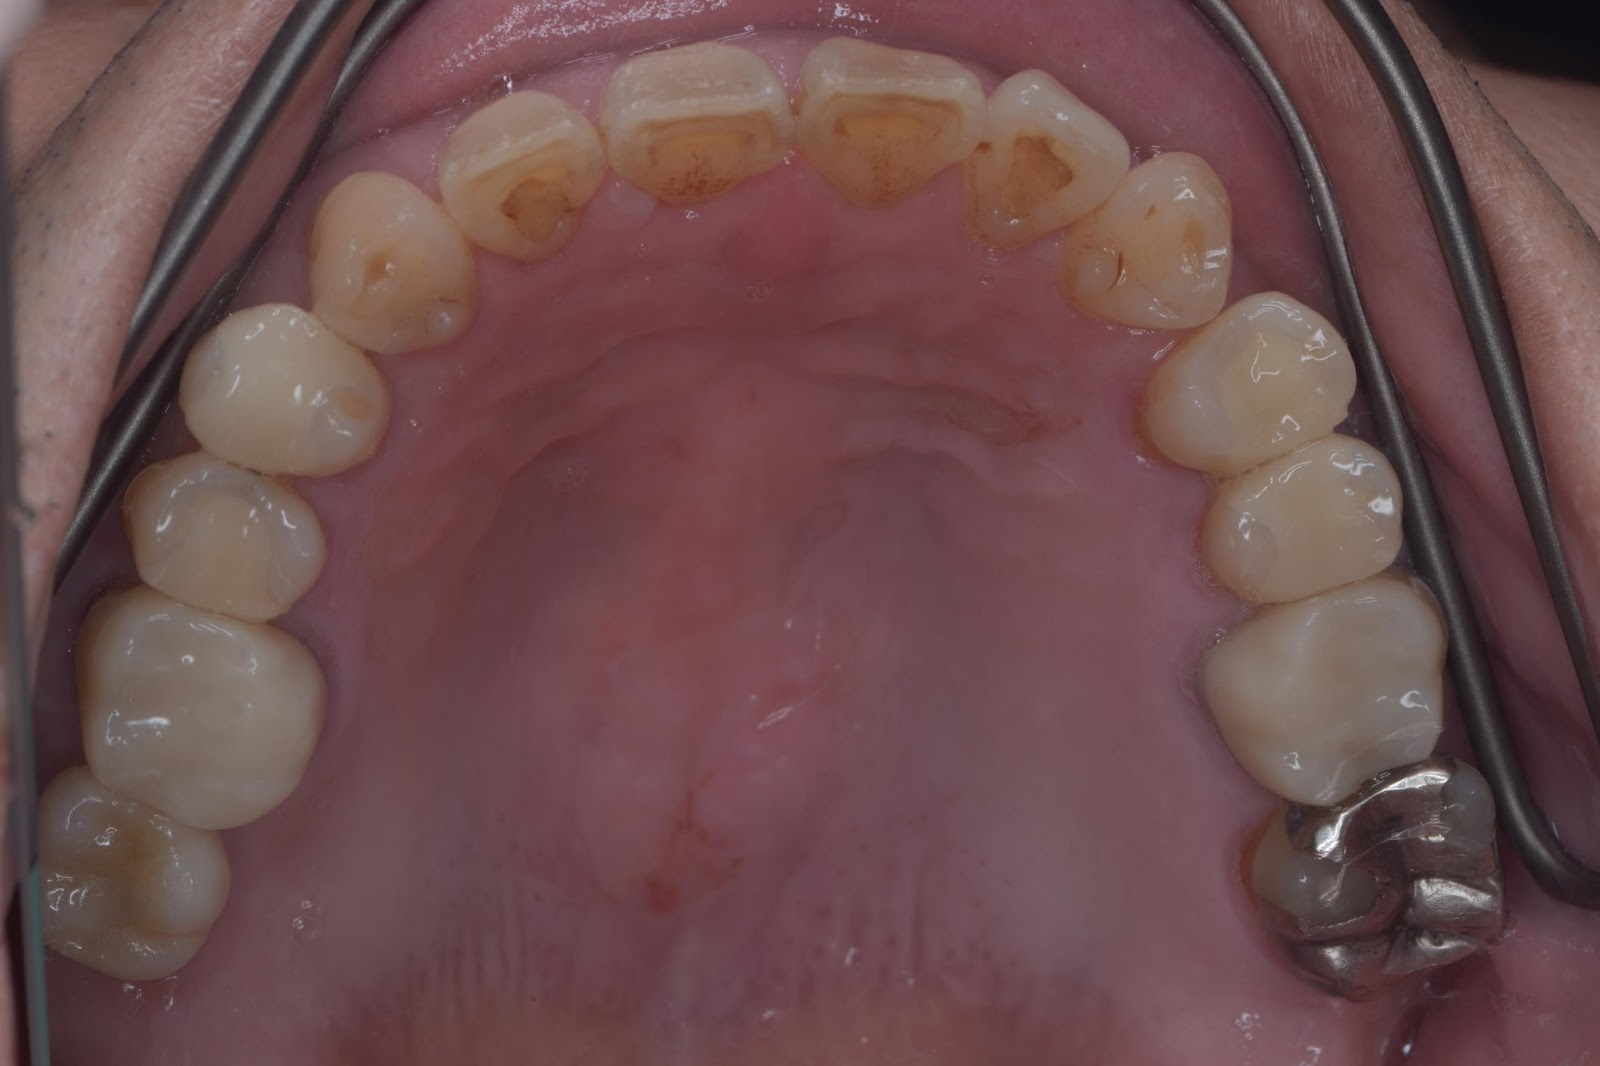

上部構造セット後(上)